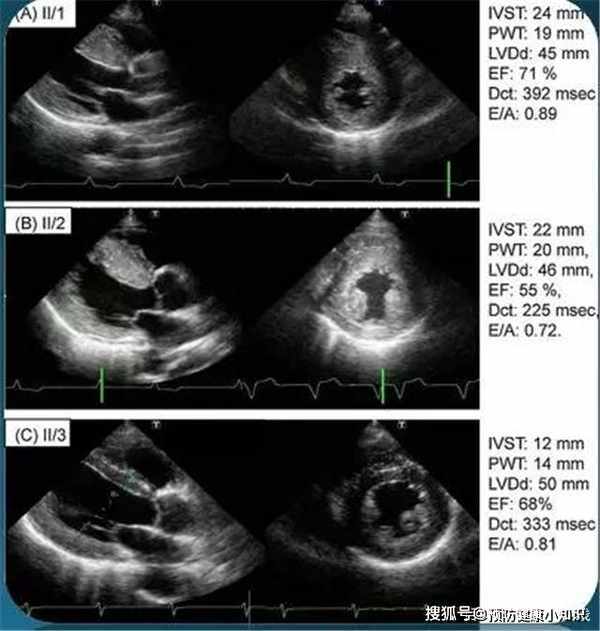

醫生說完之後就安排蔡大爺做了血壓、血脂和心電圖的檢測,根據檢查報告和對蔡大爺日常生活習慣的結合,醫生整理了他的病例:左心室肥厚;蛋白尿輕度升高,已達到1.2-2.0mg/dl;超聲顯示有動脈粥樣硬化的迹象;高血壓視網膜病變嚴重。